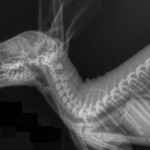

The Whyalla Veterinary Clinic has a new Shimadzu MUX10 Xray machine for high quality radiographs and a new Agfa XD14 Csi Tethered panel to produce outstanding direct digital Xrays from the images from the Shimadzu MUX10 Xray machine.

The XD14 CsI Tethered Panel is an integral part of an Agfa HealthCare’s Instant DR solution, which includes the NX image acquisition software with MUSICA3 processing and detector. These cassette-less and filmless solutions provide a range of workflow benefits that improve quality, productivity and speed up exam time.